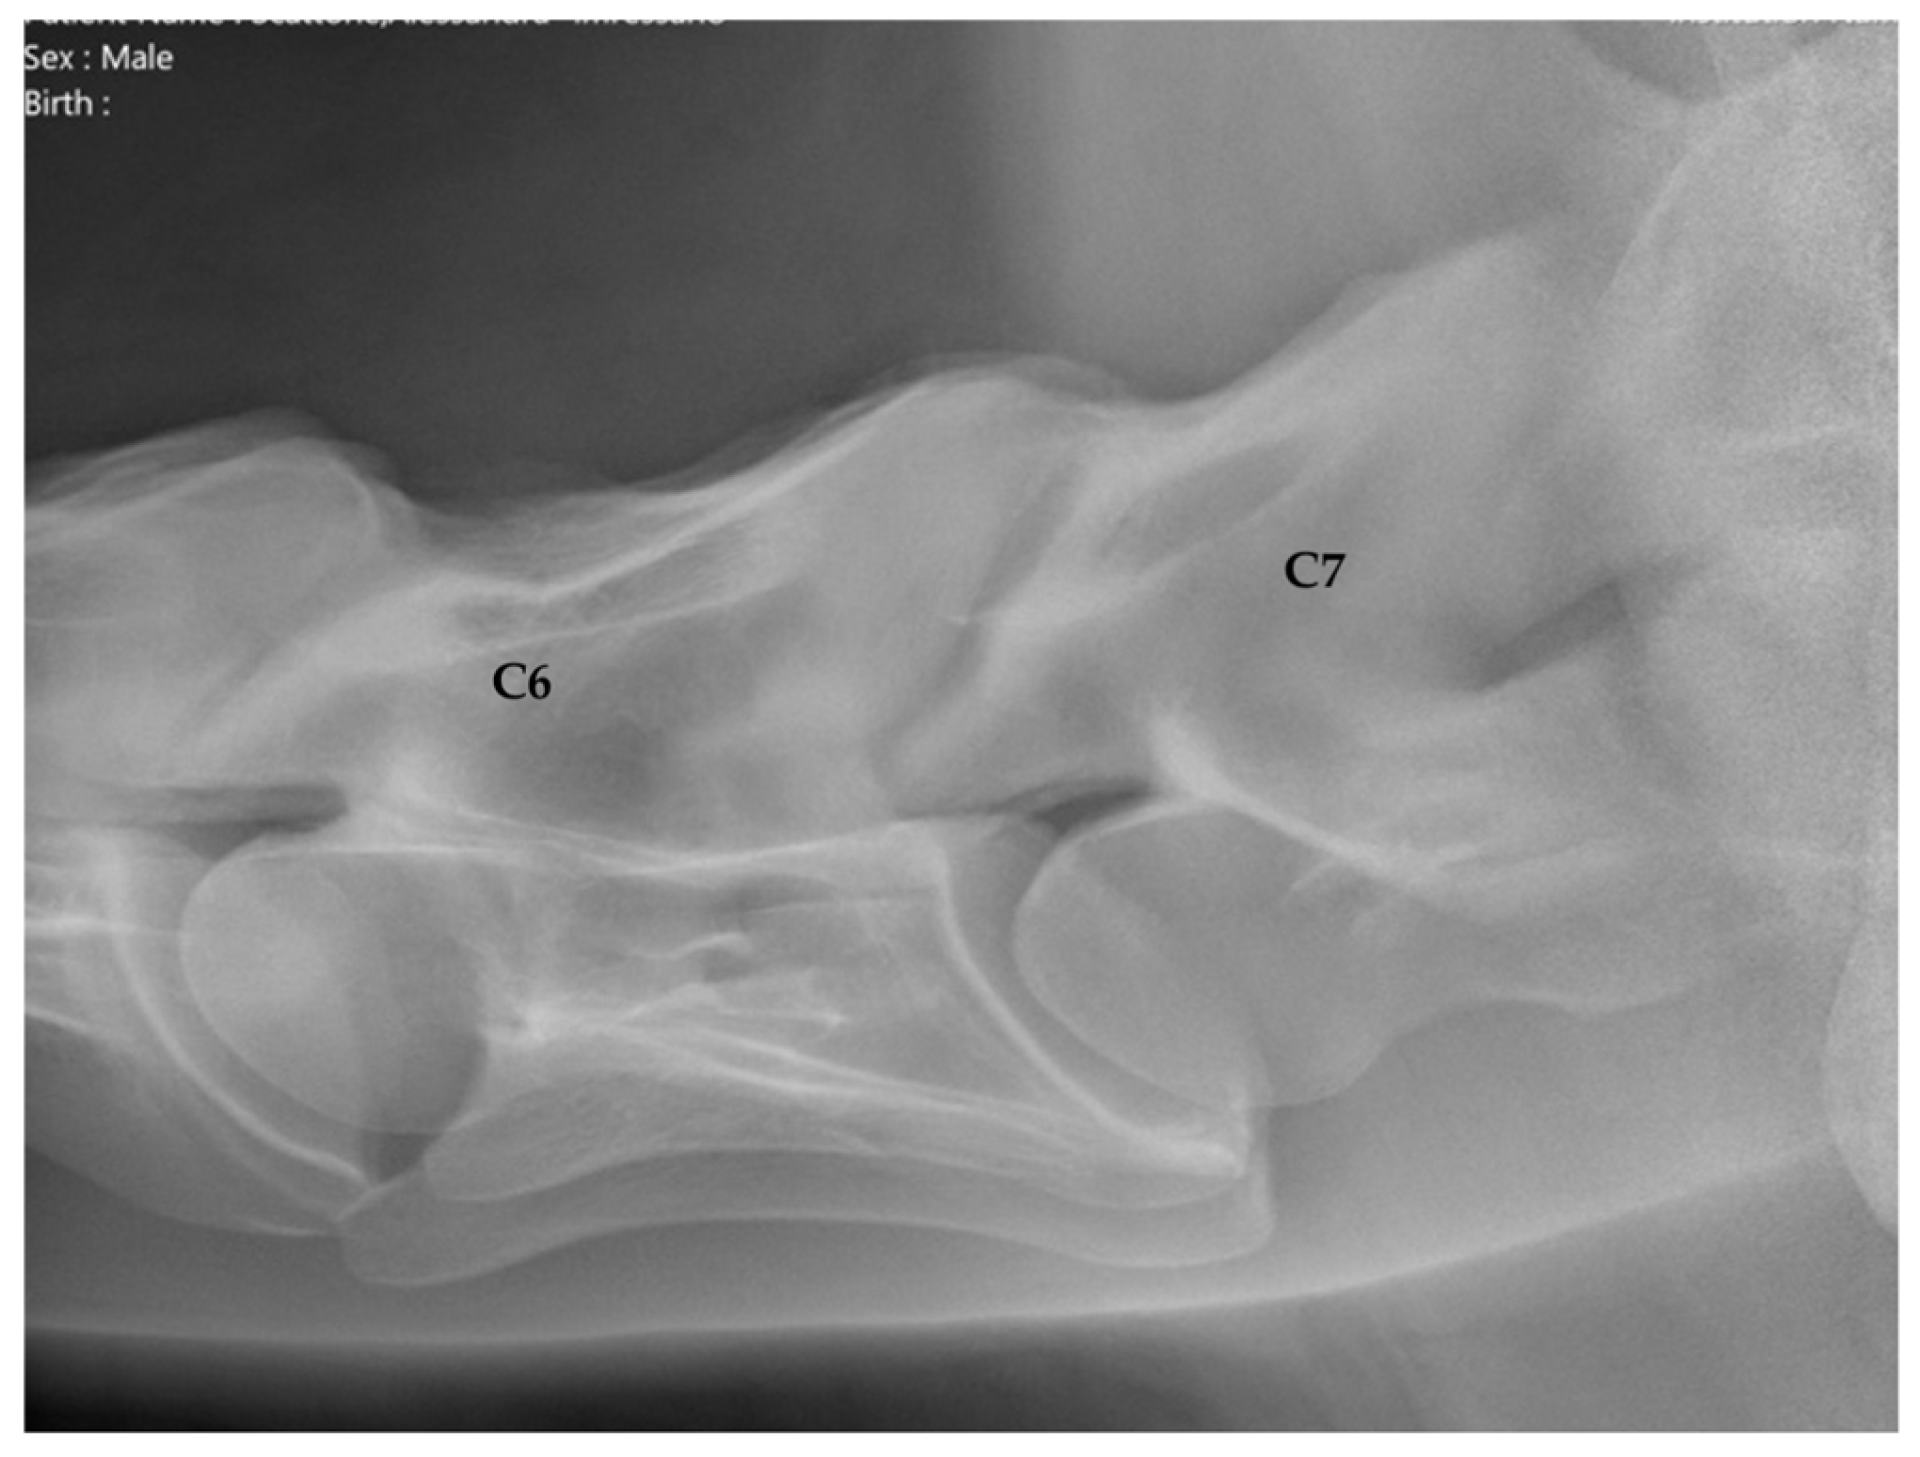

2.1.2. Radiographic Assessment

- Group 1 = normal: no periarticular new bone formation at ventral margins of APJ, intervertebral foramina clearly visible.

- Group 2 = mild APM: minimal/equivocal enlargement and sclerosis of APJ with mild osteophytosis ventrally, intervertebral foramina open/slightly obscured by new bone formation.

- Group 3 = moderate/severe APM: clear enlargement and sclerosis of APJ with moderate osteophytosis ventrally, significant reduction/loss of intervertebral foramina.